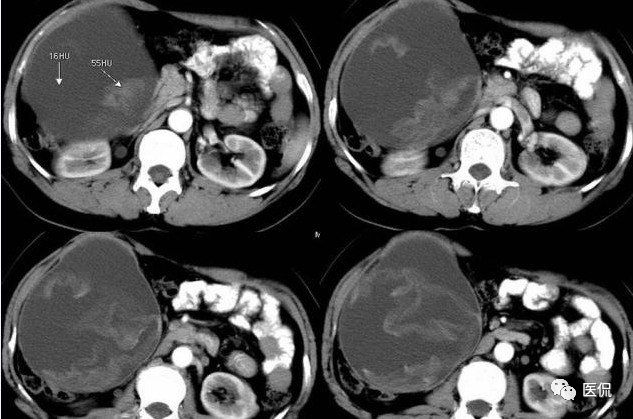

腹腔内残留的纱布在人体内引起渗出或液化坏死并纤维包裹形成异物性脓肿(纱布瘤)。纱布瘤的影像特点:圆形或卵圆形肿块,较大,有完整包膜,薄壁,较少的情况下为厚壁,边界较完整,增强后薄膜可以持续强化。不同时期的纱布瘤可以有不同表现:早期(10个月或半年内)多表现为蜂窝状;2~5年内一般表现为囊性飘带状;10~20年之后则为实性软组织密度,包膜钙化呈钙化网状结构。手术过程中残留在人体内的医用纱布所形成的肿瘤样病变。

腹腔内遗留纱布团的影像学表现,以B超较具特征性,其主要表现为:腹腔或盆腔内特殊率减的黑色包块,后方伴有扇形衰减的声影,上窄下宽,好似一“黑色大布”,早期包块内含有不规则光团或光点,随时间延长有缩小或消失,为纱布团内气体。CT的优势在于早期常表现为软组织密度的肿块,其内可见多少不等的气泡,随时间的延长气泡逐渐被吸收减少至消失,增强扫描可见包膜不同程度强化而内容物无强化。熟悉其影像学表现,可在术前作出明确诊断。